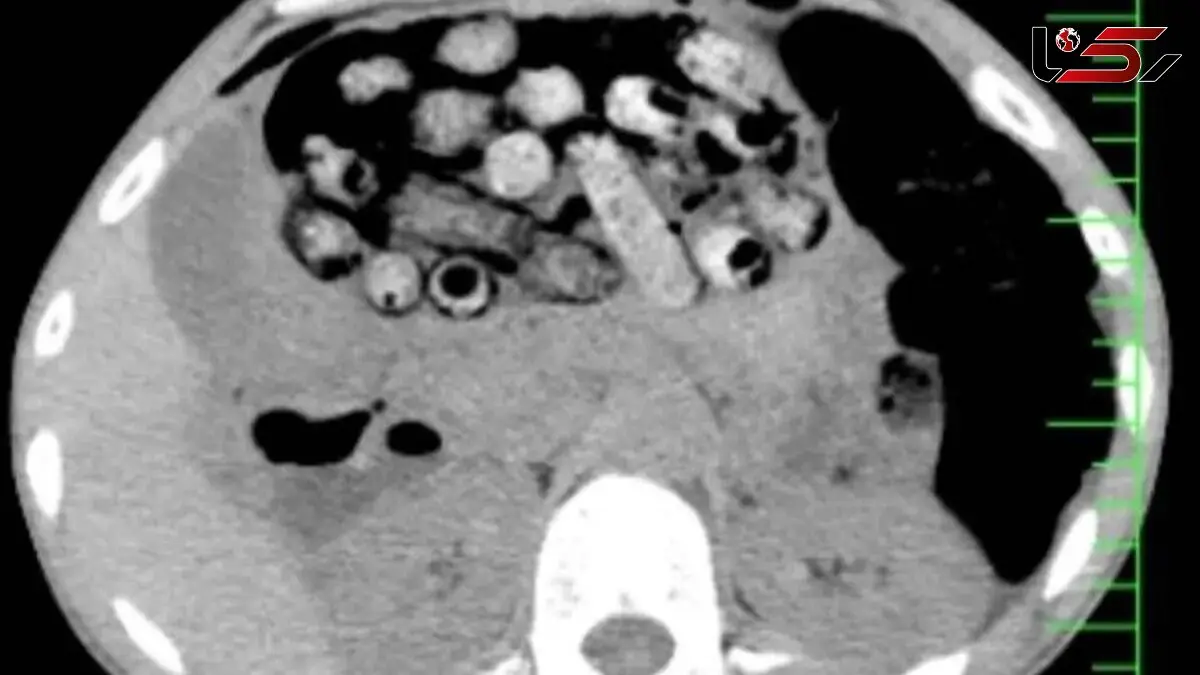

علت مراجعه بیمار مشخص شدبر اساس توضیحات مأمور همراه، این فرد پیش از ورود به بیمارستان، اقدام به بلع چندین بسته محتوی مواد مخدر کرده بود. در تصویربرداریهای انجامشده، تعداد قابلتوجهی بسته درون معده و رودههای کوچک و بزرگ او شناسایی شد.

اقدام فوری برای جلوگیری از بروز خطربه دلیل پتانسیل پارگی بستهها و خطرات جانی جدی، بیمار فوراً به اتاق عمل منتقل گردید. این عمل سخت و فوری از ساعت سه بامداد آغاز شد.

عمل جراحی موفقیتآمیزبه لطف تلاشهای دکتر سامان شیخی ، عضو هیأت علمی گروه جراحی عمومی دانشگاه علوم پزشکی البرز، و همکاری تیمهای اورژانس، تصویربرداری، بیهوشی و جراحی، ۹۰ بسته مواد مخدر از معده و روده بیمار خارج شدند.